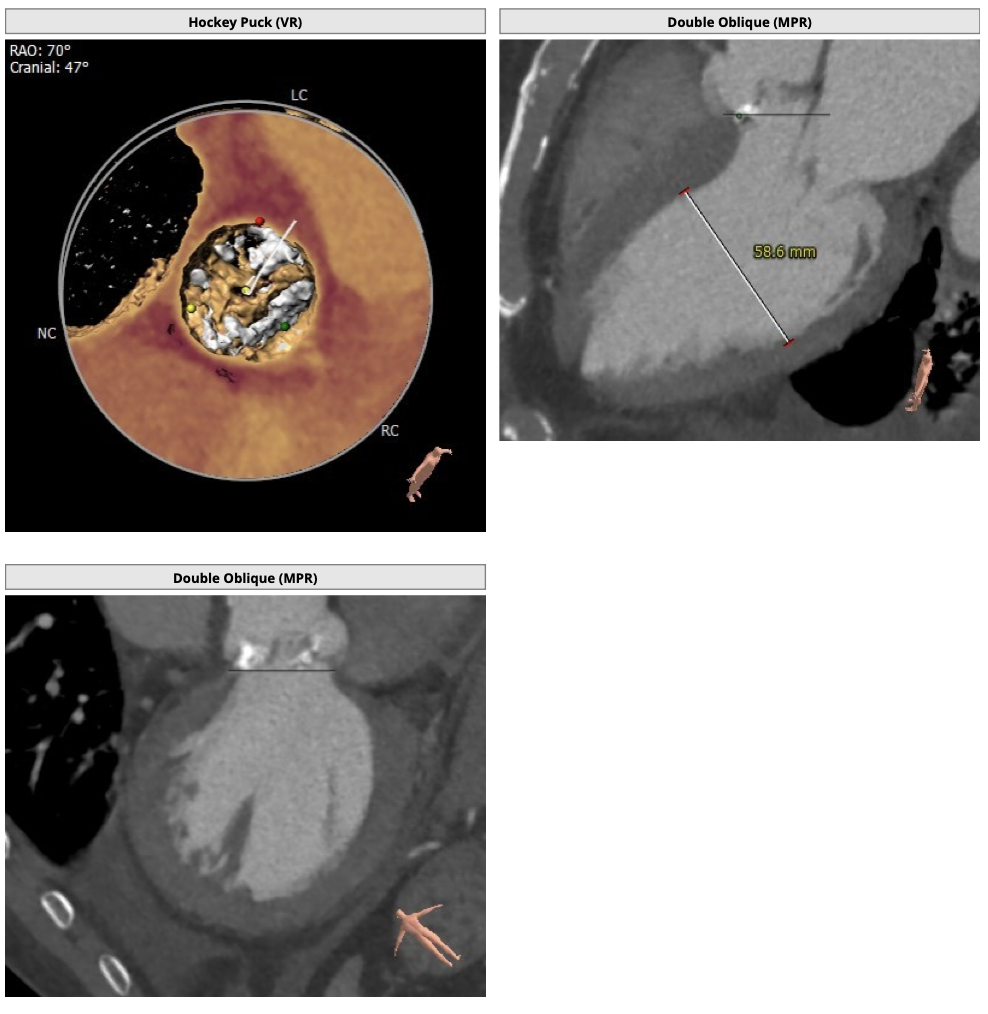

主动脉CT

患者为三叶瓣,轻度钙化,右无、左右疑似部分融合,左冠高度可,右冠高度高,法式窦结构大,左室大,升主动脉未见明显扩张,右股动脉可作为主入路。

经分析研判,根据患者的瓣环径,结合患者瓣上结构,优先选用L26号的VenusA-Valve瓣膜,备L29,使用22mm球囊预扩,根据球扩情况进一步确认选瓣,瓣膜释放后结合造影和超声情况,决定是否后扩。